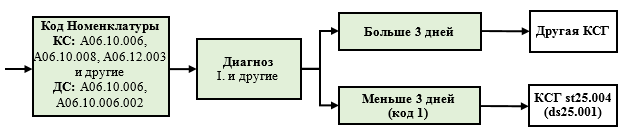

| I25.8 | A06.10.006 | 1 | st25.004 | ||||

| I25.9 | A06.10.006 | 1 | st25.004 | ||||

1.2.4. Особенности использования неполного кода МКБ 10

В Группировщике используется обозначение неполного кода МКБ 10 со знаком "." (C., I.), это означает, что могут использоваться любые знаки после точки. Так, запись C. в КСГ st36.012 "Злокачественное новообразование без специального противоопухолевого лечения" означает, что при любом диагнозе класса "С" в отсутствие иных классификационных критериев случай относится к указанной КСГ. Аналогичным образом в КСГ st25.004 "Диагностическое обследование сердечно-сосудистой системы" запись I. означает, что случай лечения с любым диагнозом соответствующего класса МКБ 10 при проведении инструментальных диагностических исследований и при длительности госпитализации менее 3 дней включительно относится к данной КСГ.